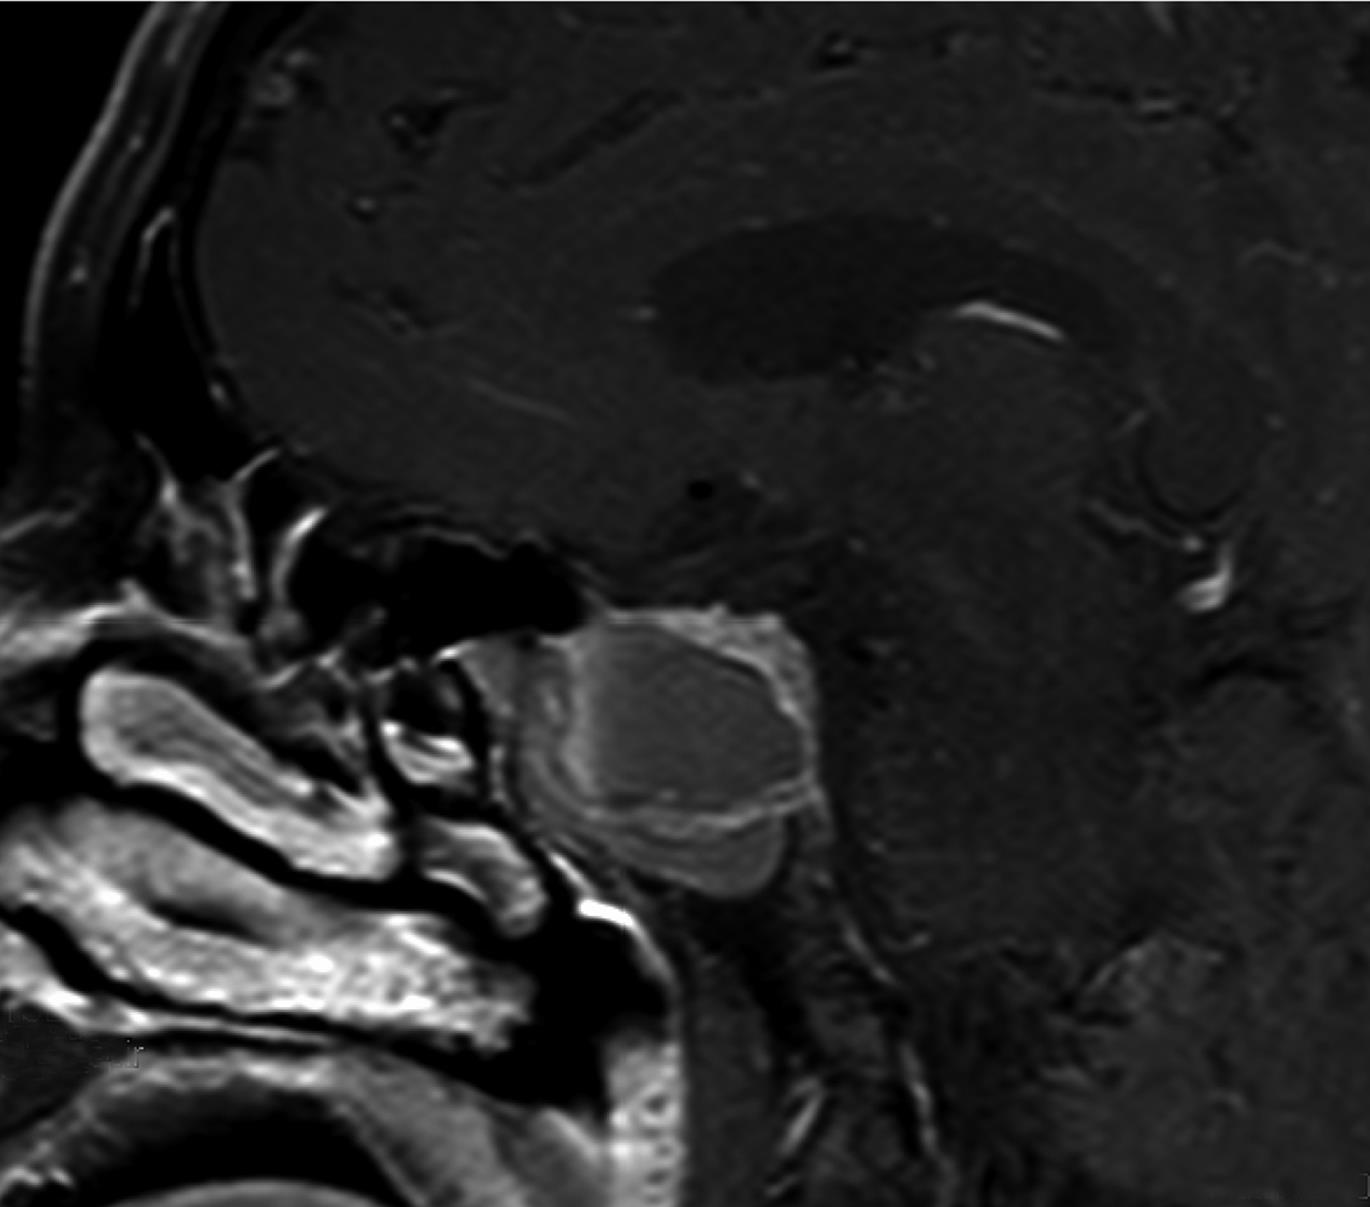

• 多巴胺受体激动剂治疗巨大垂体催乳素细胞腺瘤伴垂体卒中1例

2023, 48(9):1114-1115. DOI: 10.13406/j.cnki.cyxb.003319

摘要 (82) HTML (44) PDF 548.80 K (215) 评论 (0) 收藏

摘要:

• 0+1

• 1+1

• 2+1